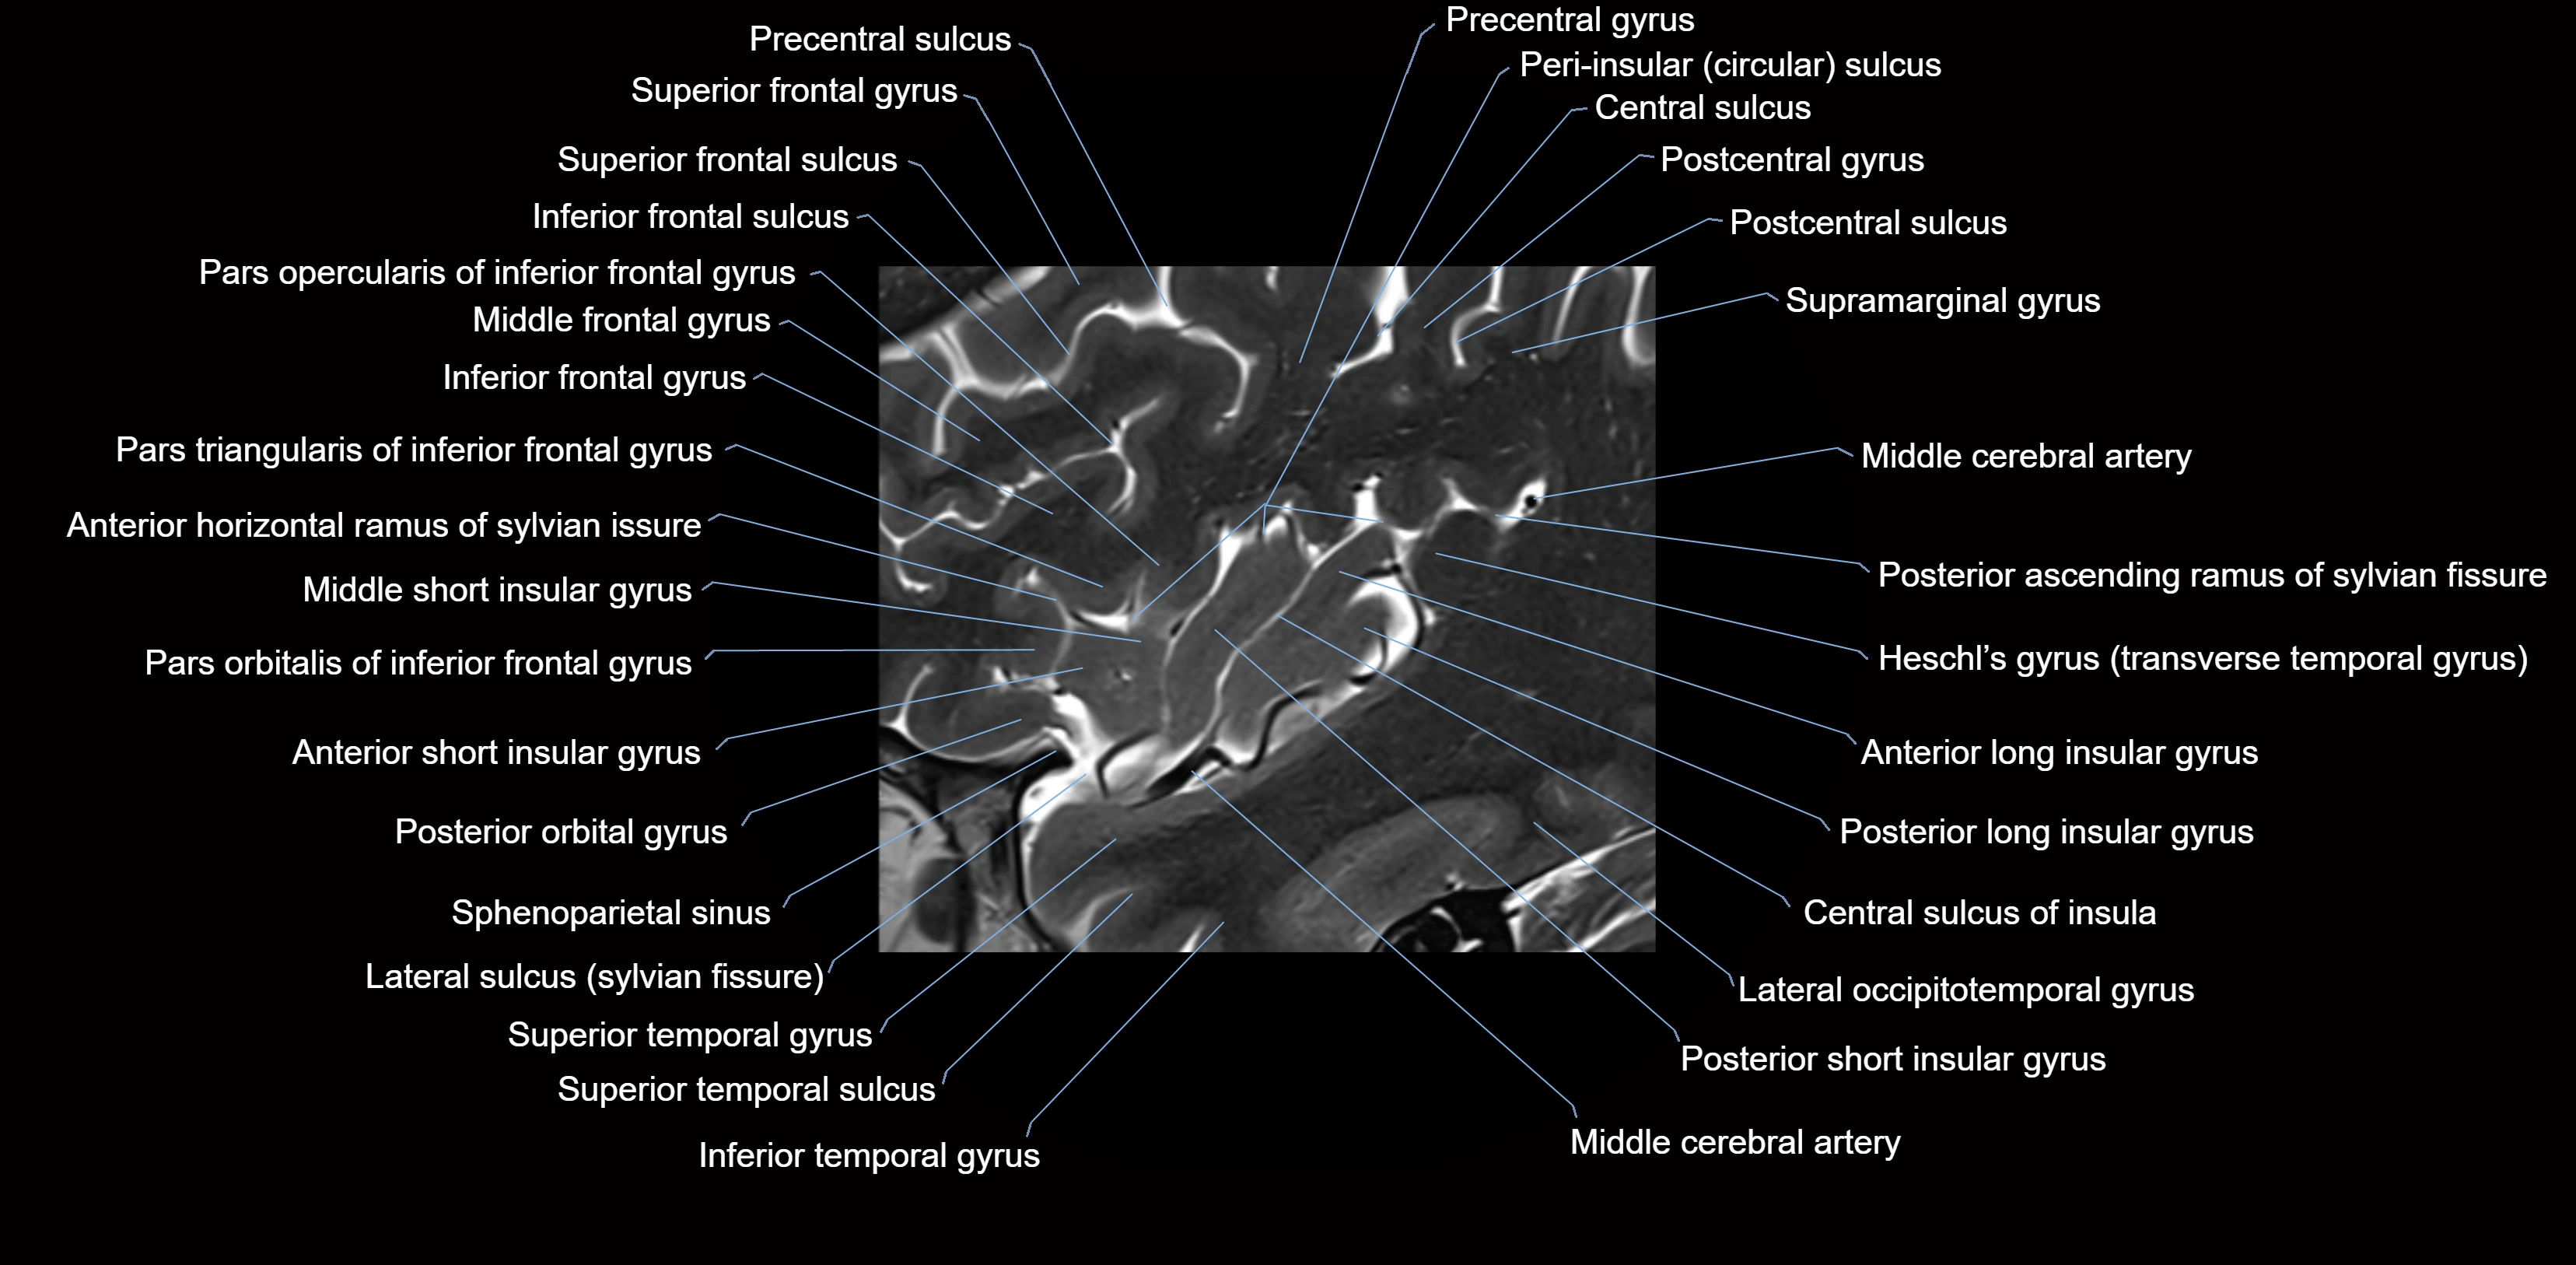

• T1-weighted imaging:

• The Sylvian fissure and its anterior ascending ramus appear as low-signal intensity (dark) CSF-filled clefts between the gyri.

• Clear demarcation between adjacent gray and white matter.

• T2-weighted imaging:

• The fissure, including the anterior ascending ramus, is hyperintense (bright) due to CSF signal.

• Better visualization of the separation between opercular and triangular parts of the inferior frontal gyrus.

• FLAIR imaging:

• The ramus is visualized as a linear dark space (suppressed CSF signal) between the surrounding cortex.

• Adjacent cortical and subcortical abnormalities (e.g., edema or gliosis) can be assessed relative to the ramus.